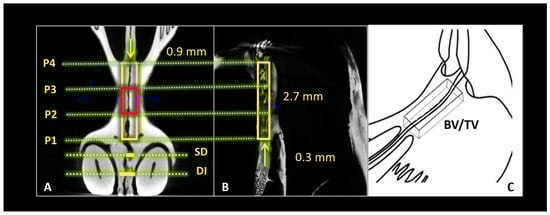

2.1. Micro-Computed Tomography